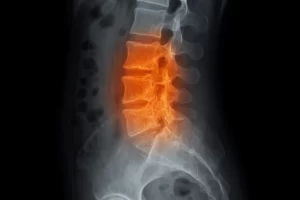

Dolor en la zona media de la espalda: Causas, síntomas y tratamientos Redaccion 30 de noviembre de 2021